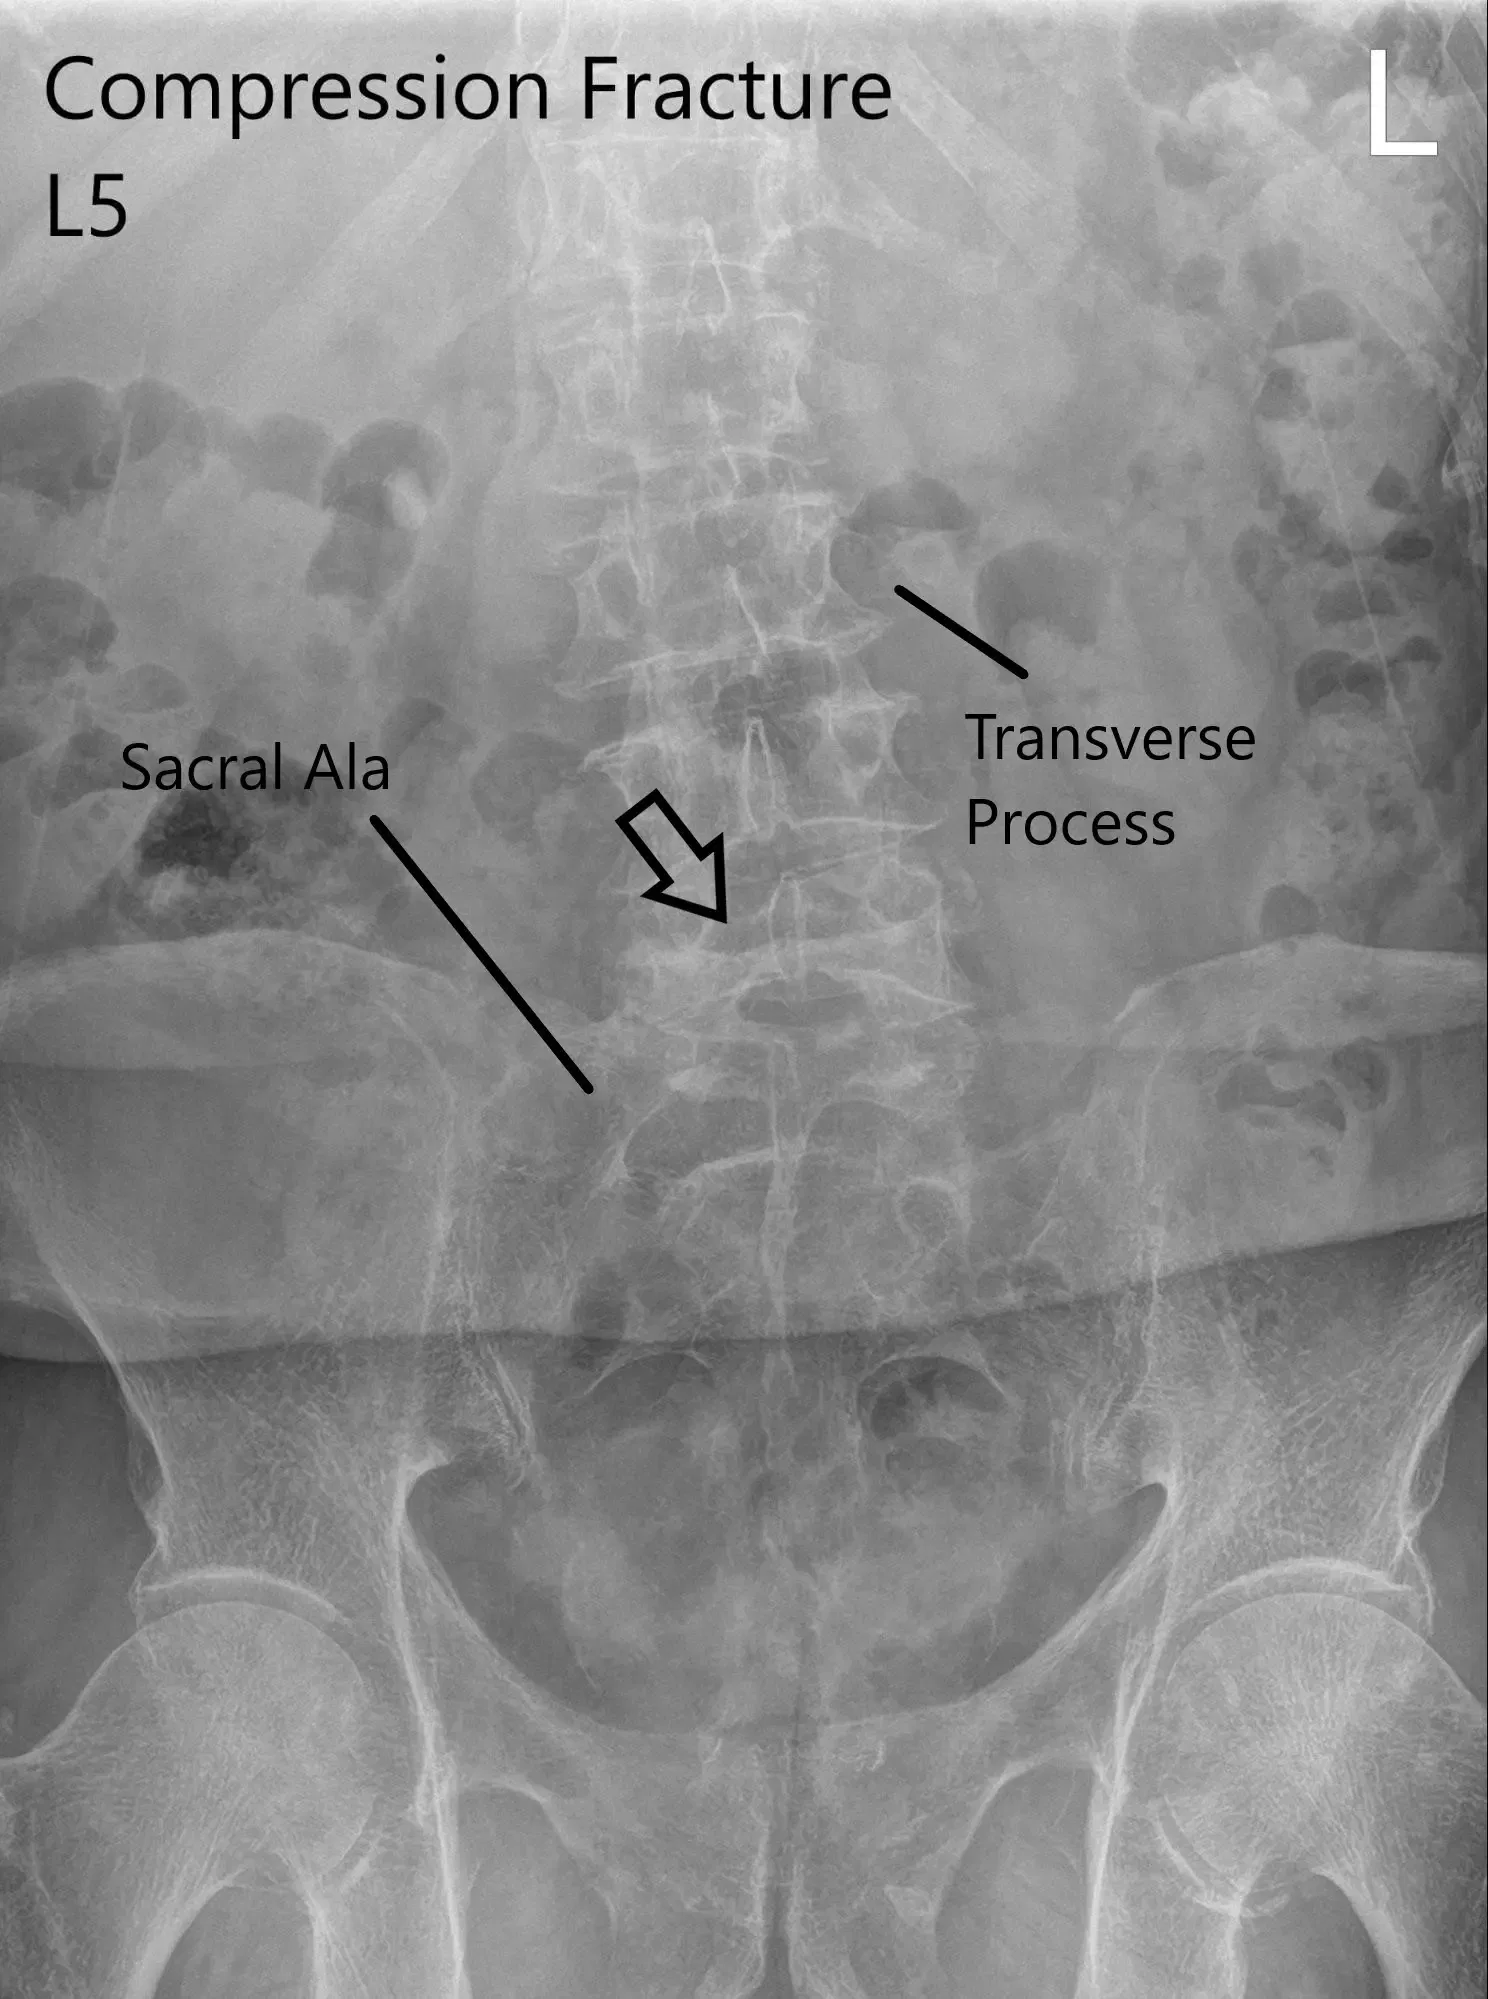

The patient is in remission from rectal cancer treated with surgery, radiotherapy, and chemotherapy. Imaging was done which showed a fracture of the L5 vertebra and severe stenosis at L3/4 and LS/S1 with severe neuro-foraminal disease and degenerative changes in the spine.

X-ray of LS spine in AP and Lateral views showing significant compression fracture L5.

CT suggested a severe compression fracture of L5 with mild retropulsion of superior endplate. Multilevel degenerative spondylosis of the lumbar spine. Moderate to severe spinal canal stenosis at L3-L4 and L4-L5 levels.

MRI lumbar spine suggested acute or subacute compression fracture at L5. Degenerative changes with multilevel spinal canal or neural foraminal, subarticular recess stenosis were also present at L4-5 and L5-S1.